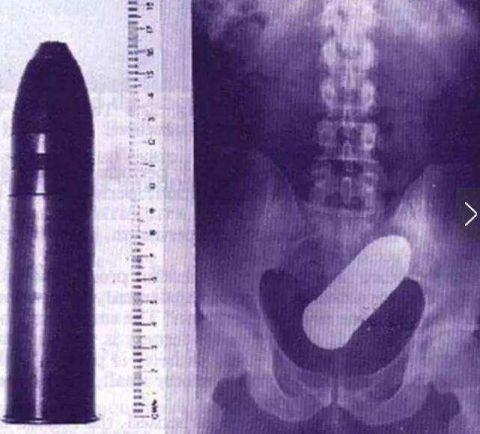

*弹子**壳